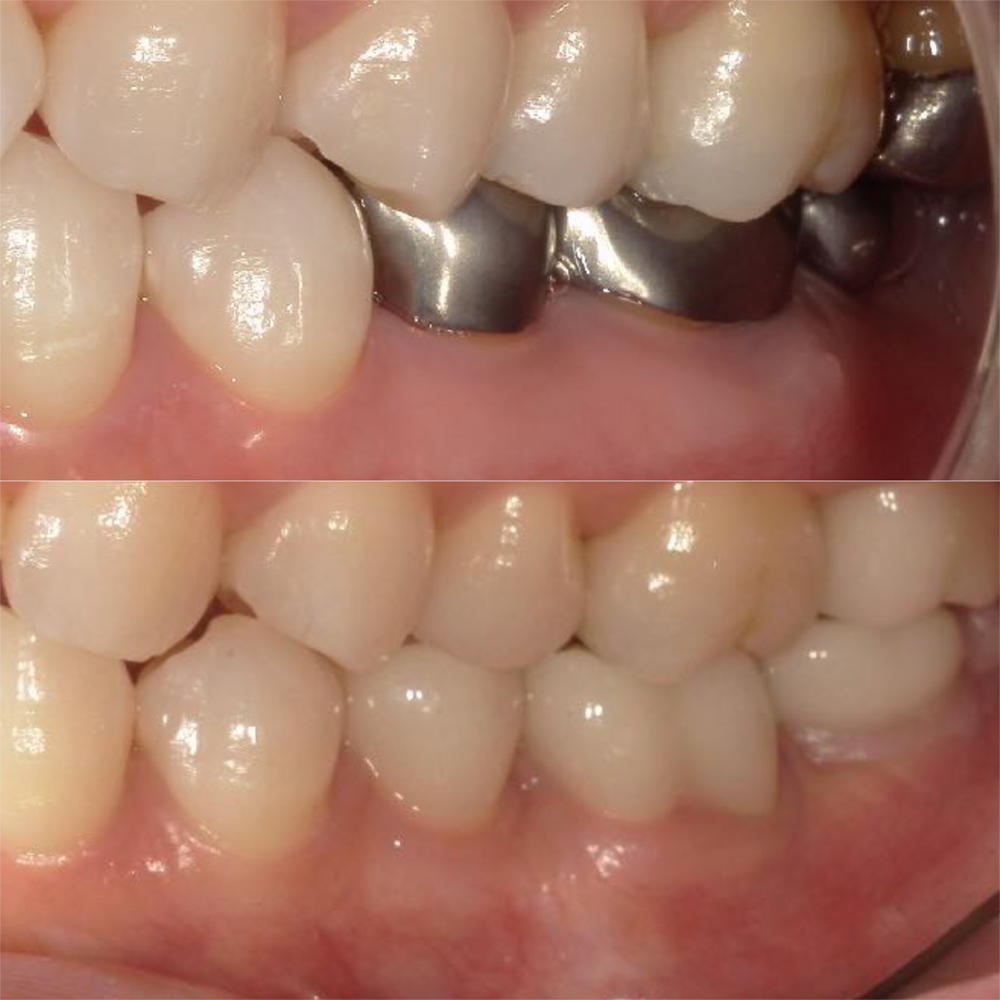

左下5、6番目

治療の内容:歯の高さが足りなく、かぶせものが外れやすい状況にある場合、 歯の高さを確保するために歯茎を下げる外科処置を行います。

治療の期間:4か月

回数:5回

金額:クラウンレングスニング2歯 66000円 、セラミッククラウン2歯 220,000円